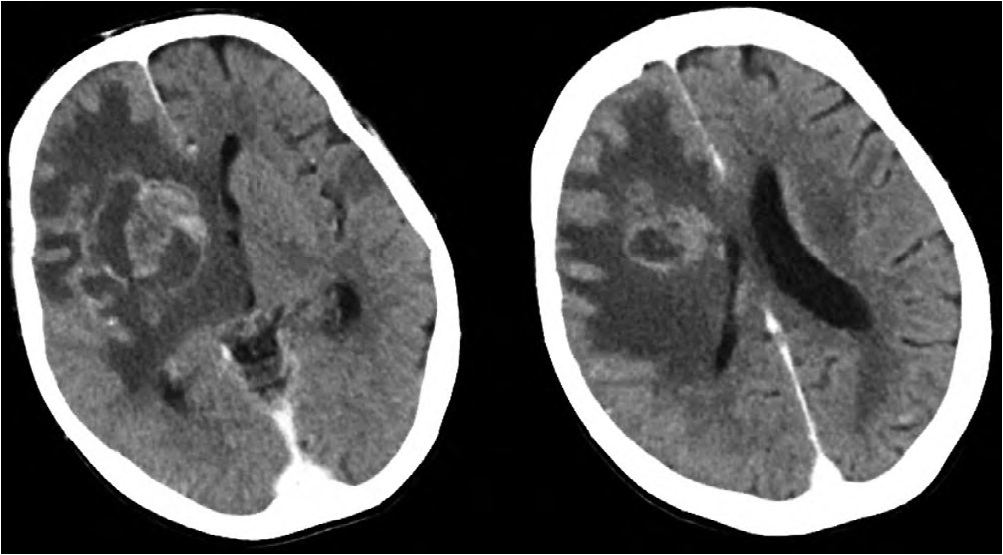

Пациентка Р., 61 год, поступила в приёмный покой Краевой клинической больницы с нарушениями речи и правосторонним гемипарезом. Со слов сопровождающего родственника известно, что она болеет на протяжении 3 нед, когда появились и стали нарастать головная боль и слабость в правых конечностях. В неврологическом статусе при поступлении: сознание ясное, сенсомоторная афазия, правосторонний гемипарез со снижением мышечной силы до 3 баллов. Выполнена МСКТ головного мозга, по результатам которой визуализировано кольцевидно накапливающее контрастное вещество объёмное образование левой лобной доли с выраженным перифокальным отёком (рис. 2).

Рис. 2. МСКТ головного мозга пациентки Р. с контрастным усилением при поступлении.

Определяется объёмное образование левой лобной доли с выраженным перифокальным отёком, кольцевидно накапливающее контрастное вещество.

Fig. 2. Сontrast-enhanced brain MSCT image of patient R. at admission.

A mass in the left frontal area, with a ring contrast enhancement and significant perifocal edema.

Через 1 мес пациентка доставлена бригадой скорой помощи в тяжёлом состоянии с нарушением уровня бодрствования до глубокого оглушения и грубым правосторонним гемипарезом (мышечная сила 2 балла). По данным МСКТ визуализированы 3 очага, кольцевидно накапливающие контрастное вещество, с выраженным перифокальным отёком. Учитывая результаты ИГХ, данное состояние расценено как множественные абсцессы головного мозга (рис. 3).

Рис. 3. МСКТ головного мозга пациентки Р. с контрастным усилением через 1 мес после операции.

Стрелки — объёмные образования обеих лобных и правой теменной долей с выраженным перифокальным отёком, кольцевидно накапливающие контрастное вещество.

Fig. 3. Contrast-enhanced brain MSCT image one month postoperatively.

Arrows — masses in both frontal areаs and in the right parietal lobe, with a ring contrast enhancement and significant perifocal edema.